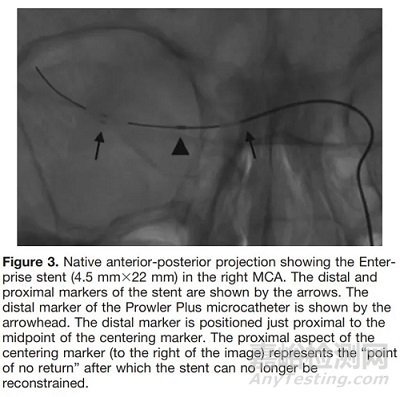

Kelly等人首次報道了使用Enterprise支架(Codman,Raynham,MA)進行一個臨時血流再通的手術,該技術提供了立即的血流恢復,而無需永久性植入支架[2]。這項技術的另一個優(yōu)點是可以在再血栓形成的情況下重新定位支架。

支架取栓器的設計與制造

(半釋放Enterprise)